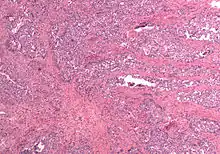

In gross appearance, MMMTs are fleshier than adenocarcinomas, may be bulky and polypoid, and sometimes protrude through the cervical os. On histology, the tumors consist of adenocarcinoma (endometrioid, serous or clear cell) mixed with the malignant mesenchymal (sarcoma) elements; alternatively, the tumor may contain two distinct and separate epithelial and mesenchymal components. Sarcomatous components may also mimic extrauterine tissues (e.g., striated muscle, cartilage, adipose tissue, and bone). Metastases usually contain only epithelial components.